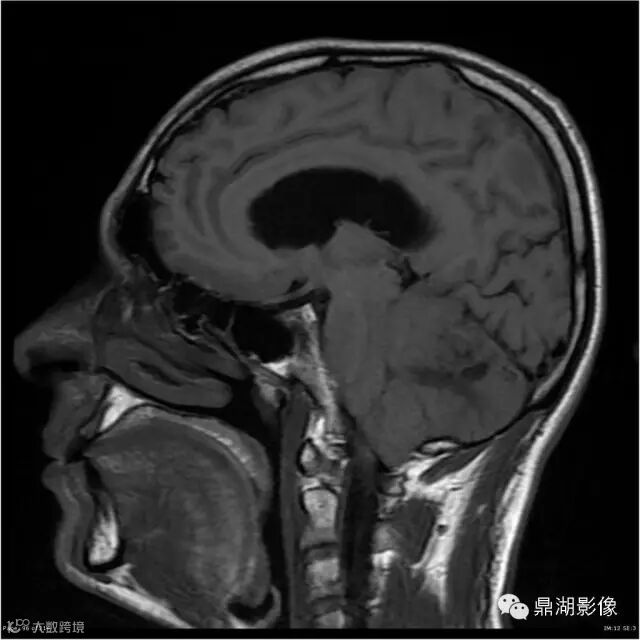

患者男,53岁,头痛、视乳头水肿伴双下肢无力。

影像:可见一个约43 x 36 x 31mm的从小脑蚓部延伸而来的占位,T1WI、T2WI呈高低混杂信号,病灶周边见流空血管影及水肿带,增强病灶明显强化,中心见无明显坏死区,它紧靠左小脑幕上。第四脑室受压变窄,室管膜水肿,可见脑桥及延脑扁桃体进入枕骨大孔。

本例为一例实质性血管母细胞瘤。实性血管母细胞瘤CT平扫示病灶呈等或高密度,增强后可见明显强化。MRI平扫通常病灶很不均质,T1呈稍低信号为主的较混杂信号,T2呈等、高信号,DWI通常呈低信号或等信号。文献报道,实性血管母细胞瘤较典型的表现为瘤内及瘤周扩张的流空血管影,瘤周中、重度水肿。因此,小脑半球区的单发肿块伴流空血管影,周围大片水肿以及增强后肿块明显强化"形态规则"边界清楚,此时应将实性血管母细胞瘤考虑在内。